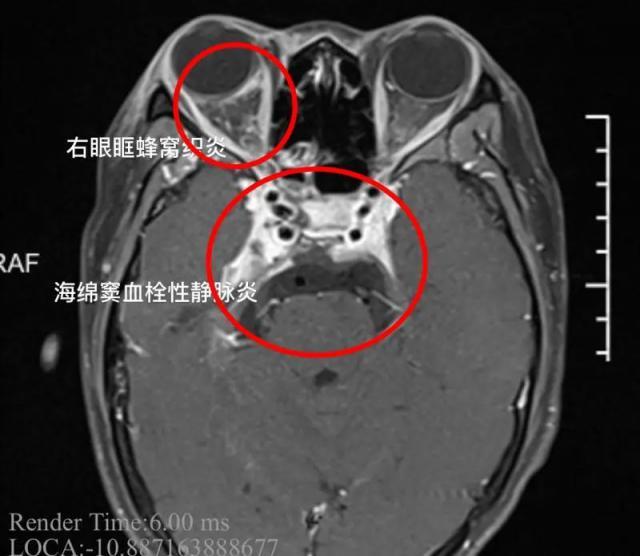

经过诊断 , 小杨患上了"海绵窦血栓性静脉炎" , 这是一种严重的颅内感染 。 该病如果没有得到及时的治疗 , 可导致患者死亡 。

患者刚来的时候 , 病情是比较严重的 , 体温持续在 39 ℃以上 , 女孩的右眼外凸 , 眼球已经固定无法转动 , 瞳孔扩大 , 对光反射消失 , 多组颅神经受累 , 这都是海绵窦严重感染的征象 。 同时我们发现患者的脑膜刺激征阳性 , 海绵窦的炎症已经扩散 , 出现了脑膜炎 , 继续进展随时有生命危险 。

小杨的头部 CT 片 。